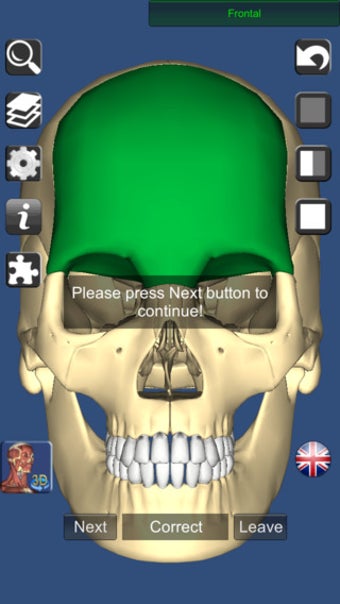

على الرغم من أنها لا تبدو رائعة مثل Essential Anatomy ، إلا أنها مفصلة مع القدرة على اعرض النص من أي زاوية strong> بالرغم من أنه يتعين عليك الترقية إلى الإصدار الكامل لمشاهدة كل شيء. p> هناك أيضًا اختبارات ثلاثية الأبعاد strong> لاختبار تكوين معرفتك 3D Anatomy Lite مصدر ممتاز للطلاب. p>